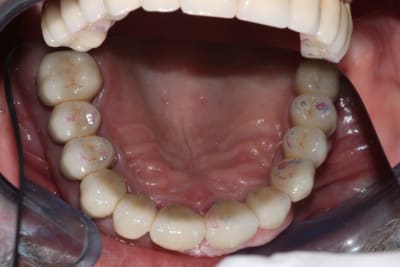

Allez, cas fini cette semaine, je vous le présente tel qu'il est arrivé.

La pano est dégueulasse, à l'époque je n'avais pas encore la mienne, merci les radiologues.

Pour compléter donc:

-pas de lésions apicales visibles, les dents non dévitalisées répondent au test de vitalité.

-Pas de poches supérieures à 6 mm.

-Pas de photo du visage pré-traitement, le patient ne sourie pas, probablement complexé, et je n'ai pas voulu en rajouter.

-Brossage moyen, ok dès la première séance après enseignement de l'hygiène.

-La 23 est foutue, cariée jusqu'au trognon.